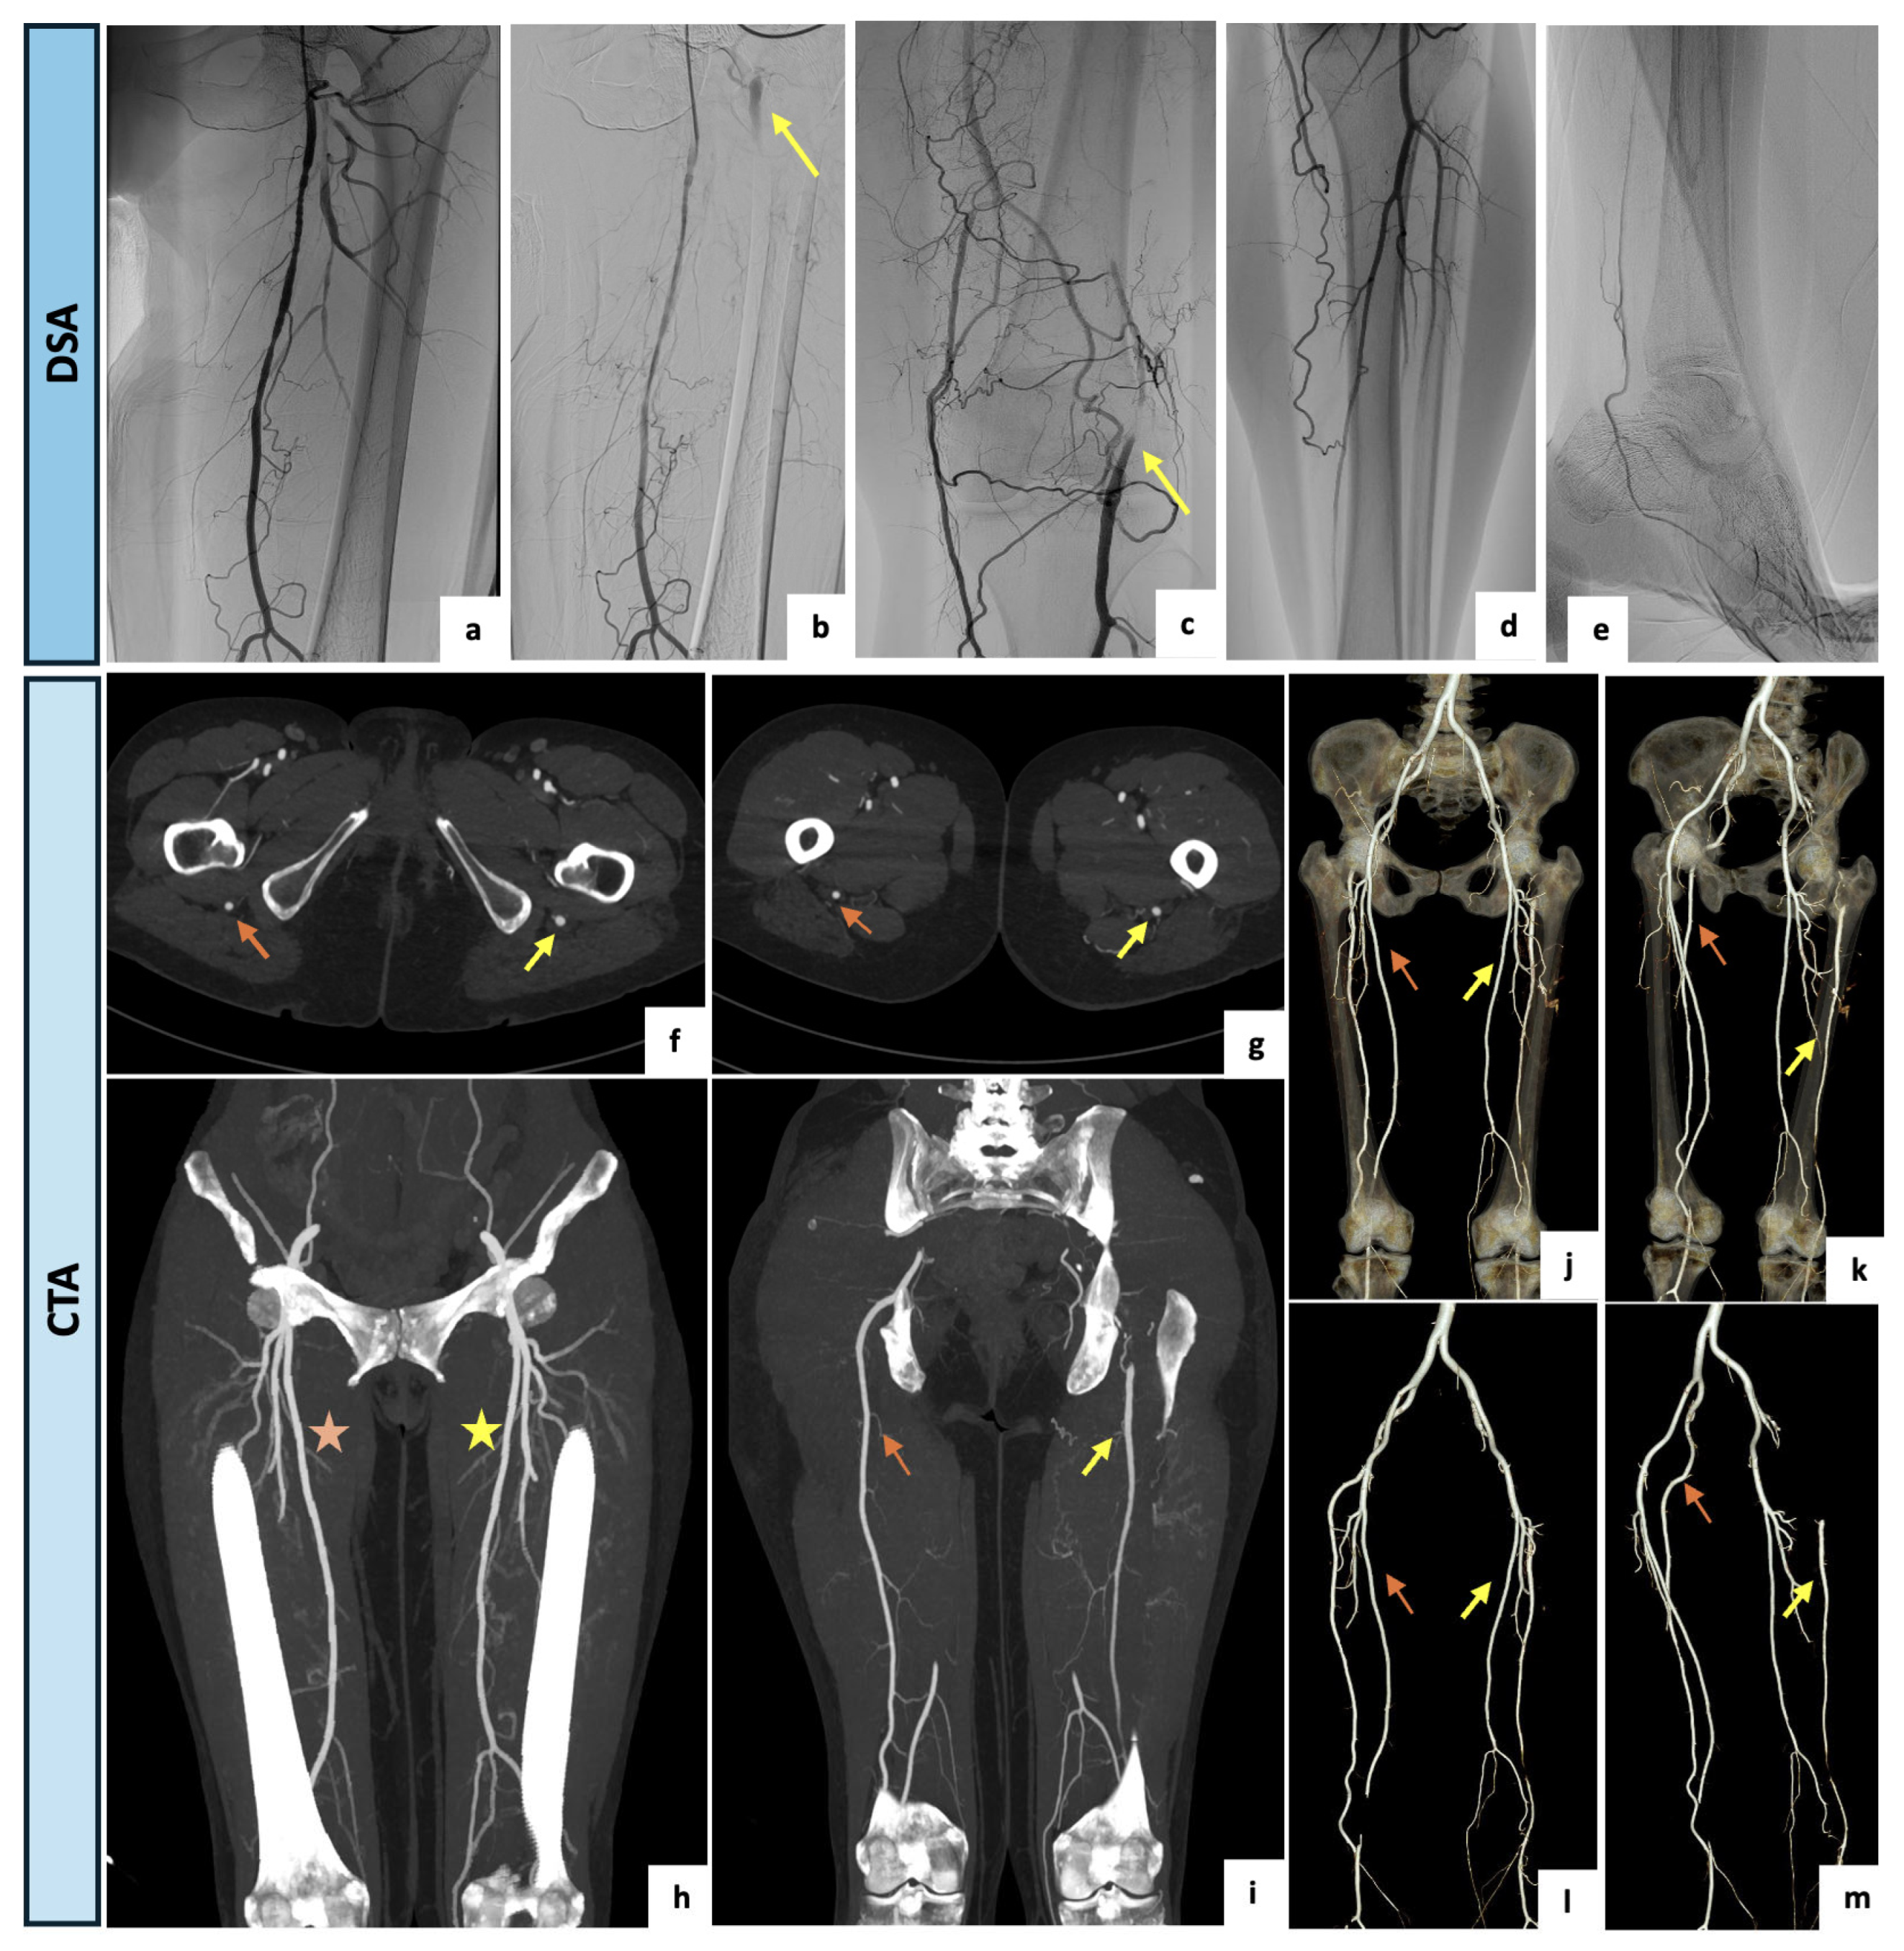

An 81-year-old female with no major comorbidities and no history of peripheral vascular disease was referred to the Emergency Department of our hospital for the presence of moderate and recurrent back pain occasionally requiring pain medication. Upon examination, the patient exhibited an antalgic gait, normal vital signs, and regular perfusion, sensation and motor function of the lower extremities. A diminished right femoral pulse in combination with a regularly palpable popliteal pulse (named Cowie’s sign) was detected. The CTA examination (Figure 4) revealed the incidental finding of a right complete PSA originating from the internal iliac artery, with an incomplete ipsilateral SFA (type 2a). In this case, the PSA had developed as an ectatic arterial continuation (13 mm) of the internal iliac axis running through the greater sciatic notch, penetrating the bundles of the gluteus maximus muscle and following the proximal course of the sciatic nerve. Distally, the PSA had a regular course as popliteal–tibial axis with the high-origin anterior tibial artery. The SFA was proximally patent but diminutive and interrupted at Hunter’s canal. Due to the absence of aneurysmal degeneration and ischemic symptoms, the case was conservatively managed with a single anti-platelet agent, timed analgesics and instructions to avoid prolonged seated positions.

Figure 4.

(a–d) Axial and coronal maximal intensity projection views of the CTA demonstrating a right complete and ectatic PSA of 13 mm (yellow arrow) originating from the internal iliac artery and accompanied by an incomplete ipsilateral SFA interrupted at Hunter’s canal (type 2a). (e) Coronal view of lower limbs with a right incomplete ipsilateral SFA (orange arrow) and a regular contralateral femoral axis (blue arrow) (f–i) Three-dimensional reconstructions showing the ectatic PSA (yellow arrow) running through the greater sciatic notch, following the proximal course of the sciatic nerve and continuing as popliteal–tibial axis.